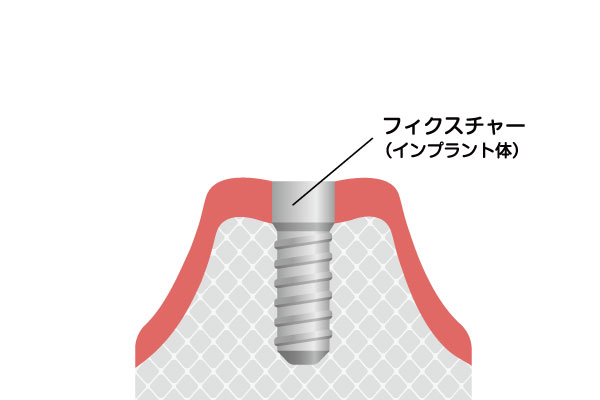

インプラントは、歯を失った部分のあごの骨に、チタンまたはチタン合金製の人工歯根を埋め込み、それを土台として人工の歯を装着する治療です。チタンは、骨としっかり結合する性質があり、生体親和性にも優れた材質です。インプラントは、人工歯根(インプラント体)、土台(アバットメント)、人工歯(上部構造)という3つの構造から成り立っており、審美的に良好なだけではなく、周囲の歯に負担をかけることなく、しっかりと噛む機能を取り戻します。